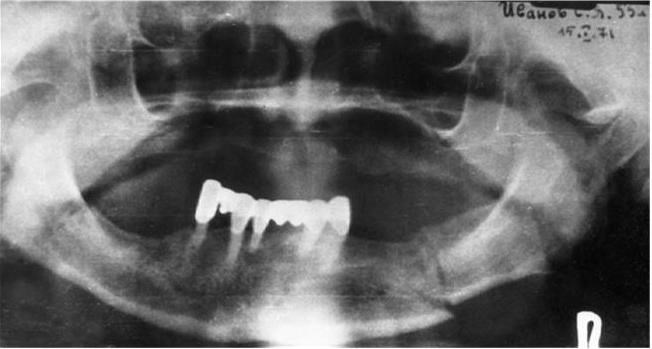

Используют также панорамную рентгенографию и, особенно, ортопантомографию нижней челюсти. Преимущество этого метода – возможность быстро получить ценную диагностическую информацию о состоянии зубов и нижней челюсти (при панорамной рентгенографии – особенно в переднем отделе челюсти).

Ортопантомографическое исследование позволяет на одном снимке проследить за изменениями, возникшими в результате перелома нижней челюсти на всем ее протяжении (рис. 5).

В настоящее время широкое распространение получил метод рентгенографии без использования рентгеновской пленки – электрорентгенография. Получаемые при этом изображения нижней челюсти вполне удовлетворяют требованиям диагностики (рис. 6), а простота и возможность быстро получить отпечаток делают этот метод очень перспективным, особенно для военно-полевой челюстно-лицевой хирургии.

Рис. 5. Ортопантомограмма нижней челюсти при множественном переломе

Рис. 6. Электрорентгенограмма нижней челюсти при переломе в области основания мыщелкового отростка справа и |34 зубов